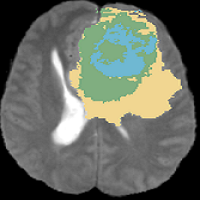

The dataset is highly imbalanced as tumor occupies small portion of the brain. The substructures of the tumor occupy an even smaller volume compared to the whole tumor. Initially, the network is trained to segment whole tumor with initialization of parameters randomly chosen from normal distribution. The obtained weights inturn are transferred to the substructure networks for parameter initialization. During each run network is trained for 50 epochs. Fig. 3 shows segmentation results for the whole tumor with three substructures(with and without inductive transfer learning) for a sample 2D slice.

Figure 3: Segmentation results: a) T2 image, (where, yellow represents Edema, blue represents Enhancing Tumor, and green represents Necrosis/Non-enhancing tumor) b) Whole tumor ground truth, c) Whole tumor segmentation, d) Edema ground truth, e) Edema segmentation without weight initialization, f) Edema segmentation with weight initialization, g) Enhancing tumor ground truth, h) Enhancing tumor segmentation without weight initialization, i) Enhancing tumor segmentation with weight initialization, j) Necrotic ground truth, k) Necrotic segmentation without weight initialization, l) Necrotic segmentation with weight initialization.